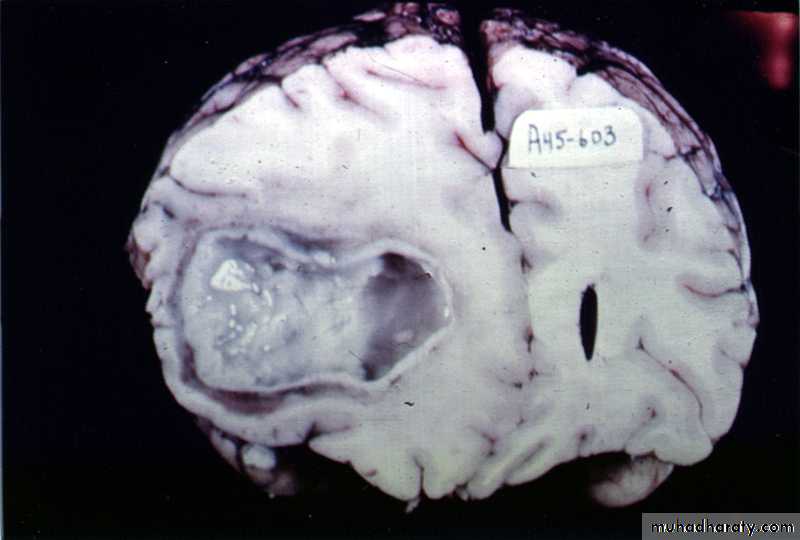

Pathology:The formation of a collagen capsule in a developing abscess is the single most important responsible that limits the spread of infection to the rest of the brain.

Collagen capsule of brain abscess

Brain Abscess Pathology

Brain abscess will pass in four stages:Early cerebritis: early 1-3 days with inflammatory cells.

Late cerebritis: days 4-9, with formation of necrotic core and increasing number of macrophages and fibroblasts.

Early capsule: days 10-13.

Late capsule (mature capsule): by day 14.